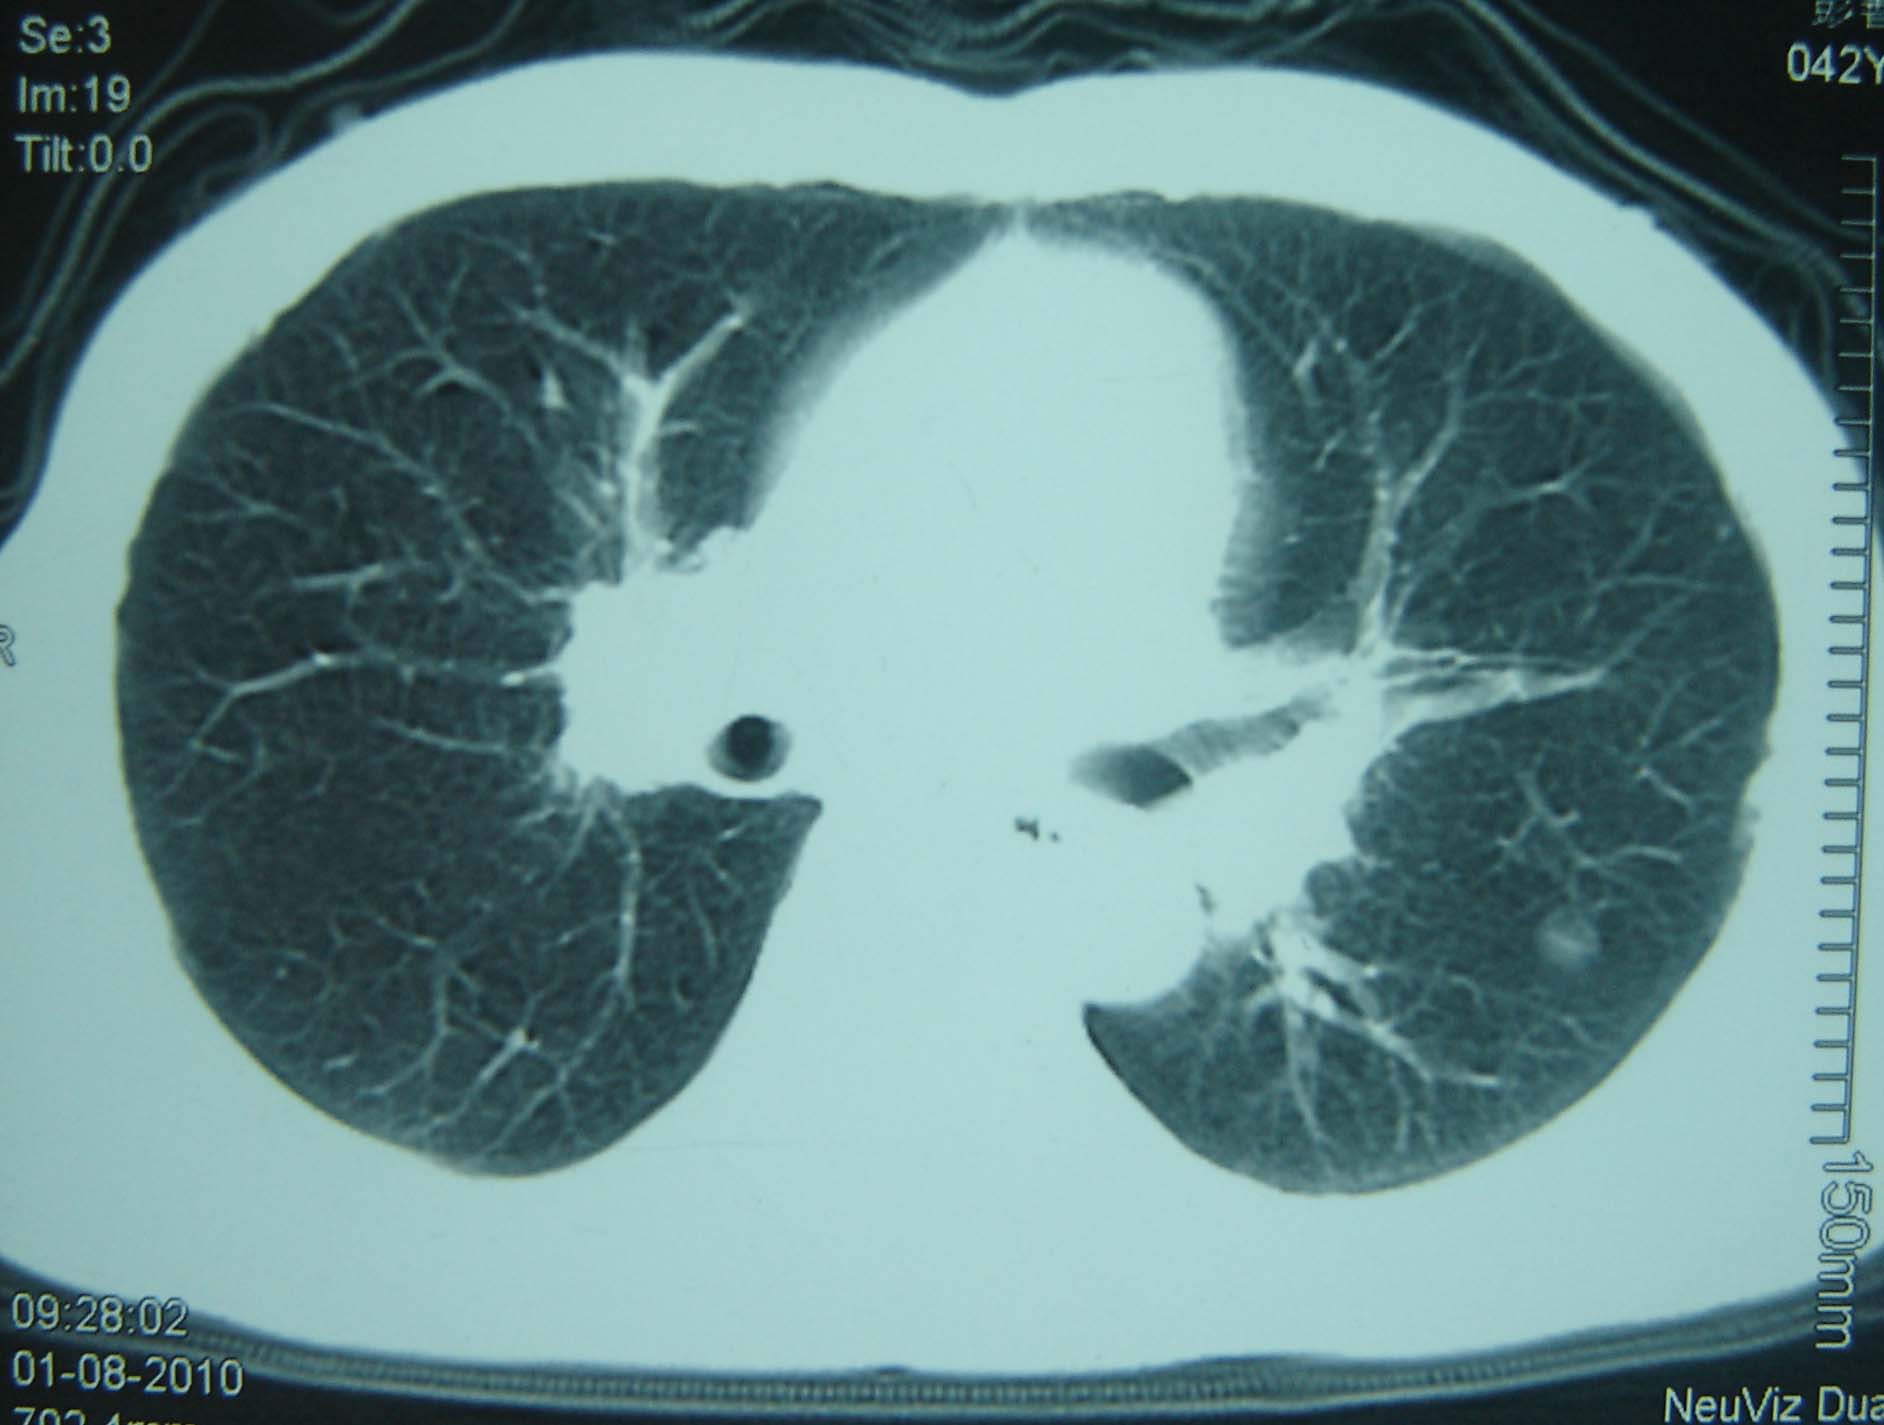

标题: CT25321:两肺多发结节 请会诊 [打印本页]

男 、43岁,咳嗽胸痛,装修工,平时接触粉尘较多,有吸烟史10多年,纤维支气管镜检查未发现异常,胃镜、腹部b超检查亦未发现异常,颈部淋巴结活检未发现肿瘤细胞。

不能排除转移,如果不能找到原发灶,只有短期随访。

结节病?转移瘤?

1)考虑双肺及胸膜多发性转移瘤。2)肺气肿。